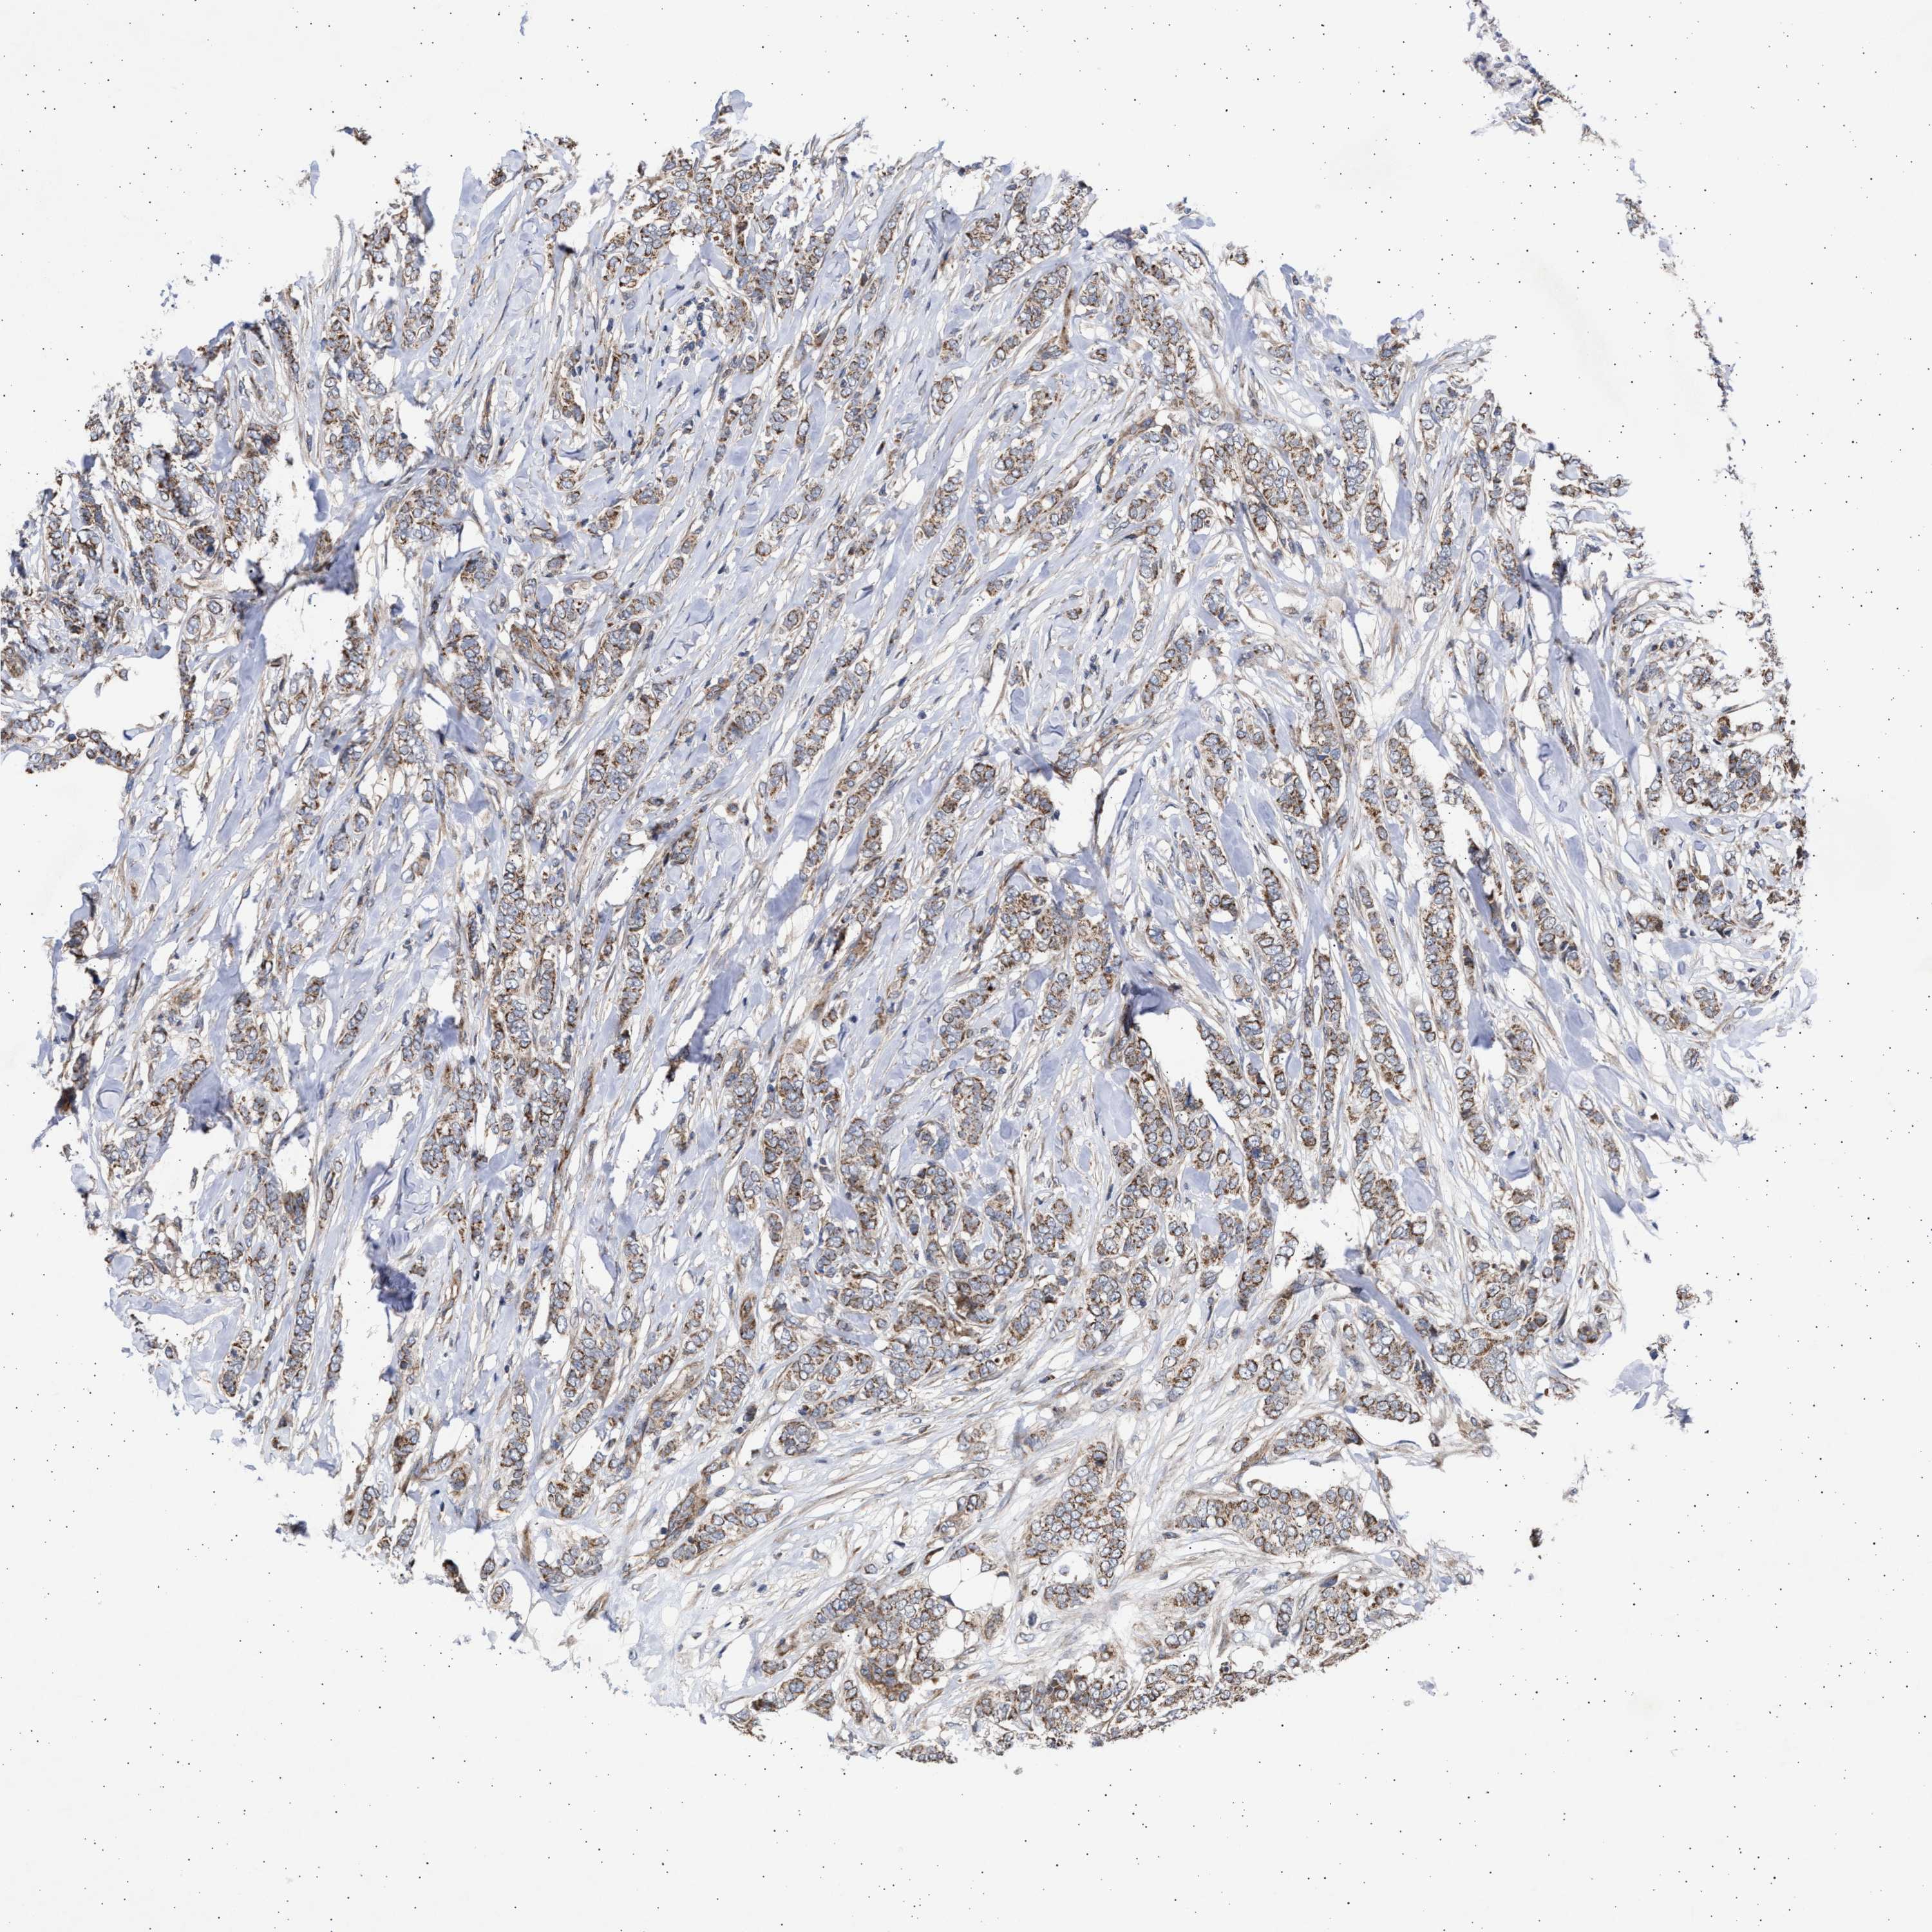

CANCER BREAST CANCER Show tissue menu

BRCA TCGA BRCA VALIDATION PROTEIN EXPRESSION